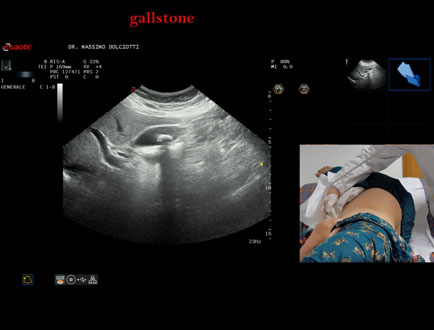

Data inserimento: 13/10/2025

Ecografia del: 07/10/2025

Strumento: Esaote MyLab Eight

Sonda: Convex Multifrequenza 1-8 MHz

Età Paziente: F 49 anni

Motivazione dell'esame: follow up per litiasi della colecisti dopo trattamento con acido ursodesossicolico.

Commento all'esame: le immagini ed il video documentano nel lume della colecisti, immagine iperecogena, delle dimensioni di 16,1 mm, con cono d'ombra posteriore, mobile al decubito, da ricondurre a litiasi.

Conclusioni: litiasi della colecisti (gallstone).

Presentazione: Dr. Massimo Dolciotti - Ancona

Elaborazione digitale: Andrea Dini - Ancona